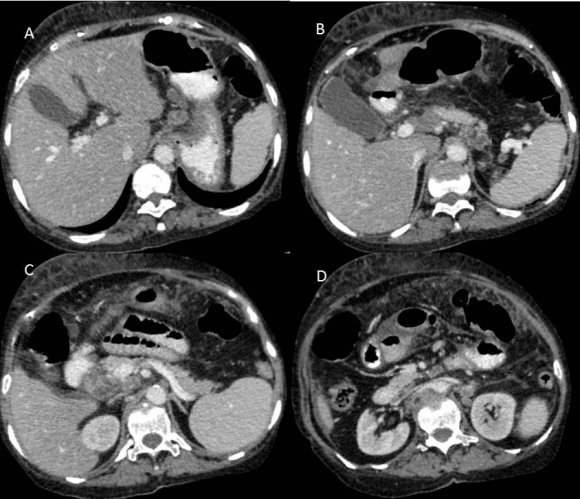

CT scan of the abdomen and pelvis (Figures: 4-8) showed changes of fatty infiltration in the liver. Multiple well-defined lymph nodes of size 1 to 2 cms were noted at portahepatis, peripancreatic region, celiac axis, left renal hilum, preaortic and para-aortic regions, precaval and paracaval regions and in right internal iliac region. Most of the lymph nodes showed peripheral enhancement with central hypodense areas of necrosis. A conglomerated matted lymph nodal mass of size 35 x 24 mm noted in the precaval region. Multiple ill-defined and nodular soft tissues infiltrate noted within the mesentery. Moderate ascites noted with mild peritoneal enhancement without septations. Ileo-caecal junction and other bowel loops appeared normal. IVC distal to renal veins showed persistent filling defect of size 10 (Anteroposterior) x 16 (Transverse) mm extending over a length of 67mm with peripheral enhancement in contrast study extending to right common iliac vein suggestive of IVC and right common iliac vein thrombosis.